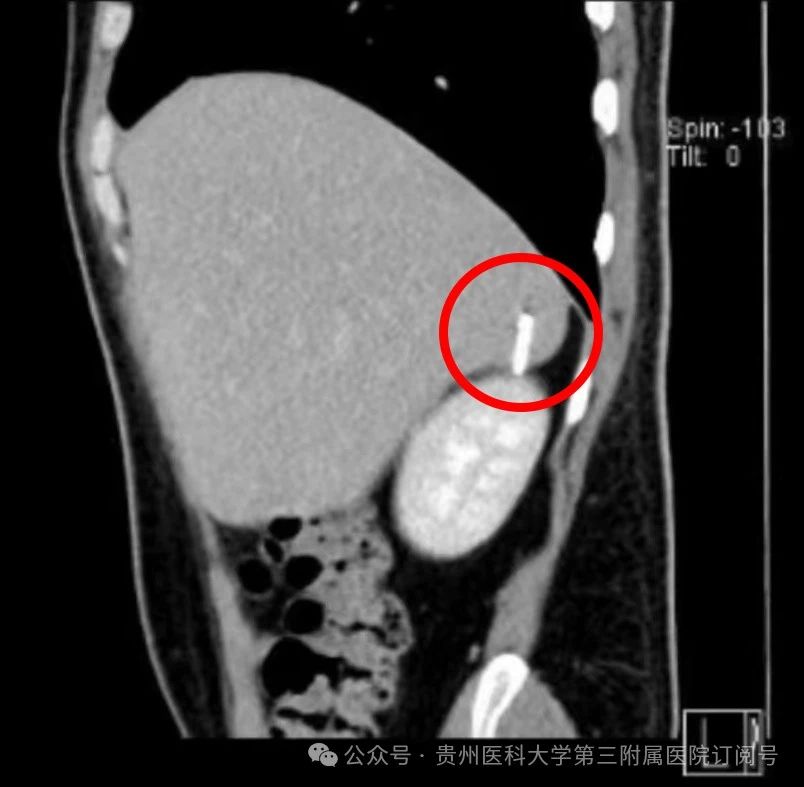

在为王先生完善了相关检查后,刘兴贵凭借着丰富的临床经验,确定了金属异物位于肝脏且毗邻肾脏处。由于肝脏血管丰富,易出现大出血情况,且金属异物在肝脏内容易游走,一旦进入肾脏,后果将不堪设想。肝胆外科经过充分讨论后,结合王先生的病情及需求,决定为王先生施行腹腔镜下肝脏异物取出术。